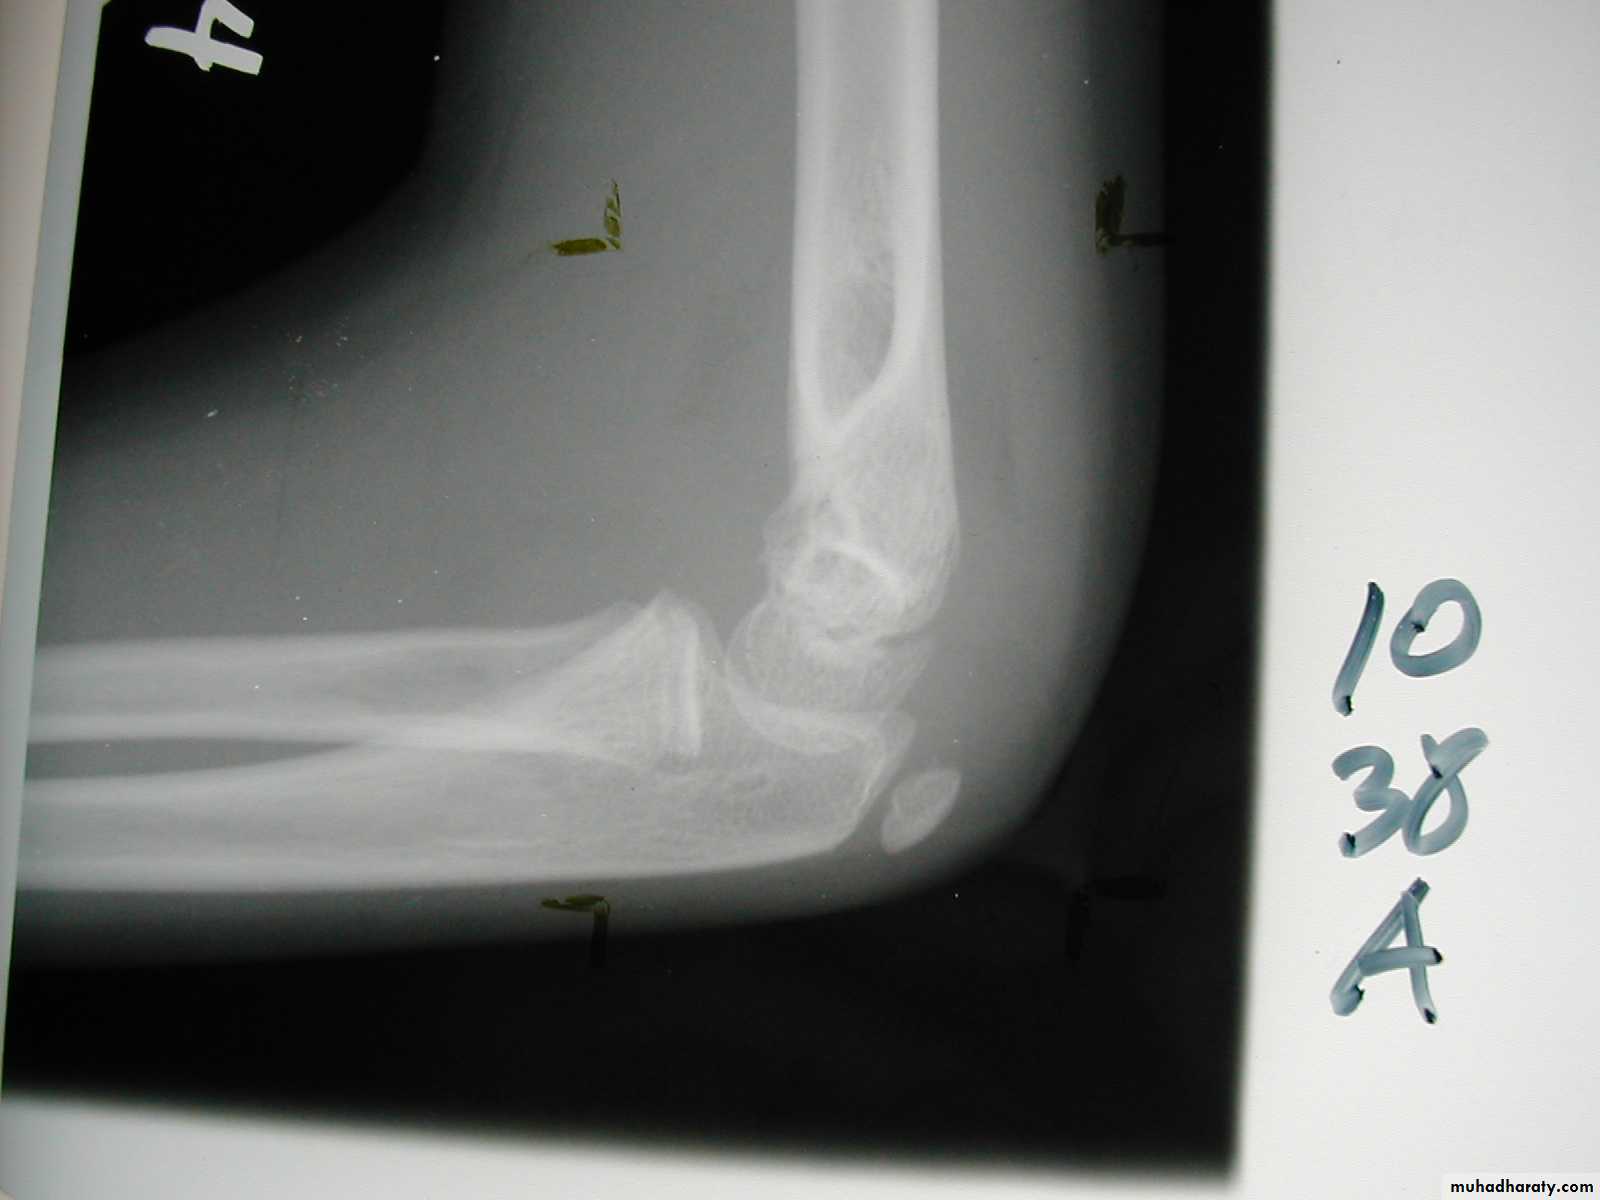

What type of supracondylar fracture

does this patient have?Flex

ionHow do the flexion patterns present?

This classical Type III pattern

is obviously a flexion injury.With these one needs to be

prepared to do an open reduction !!